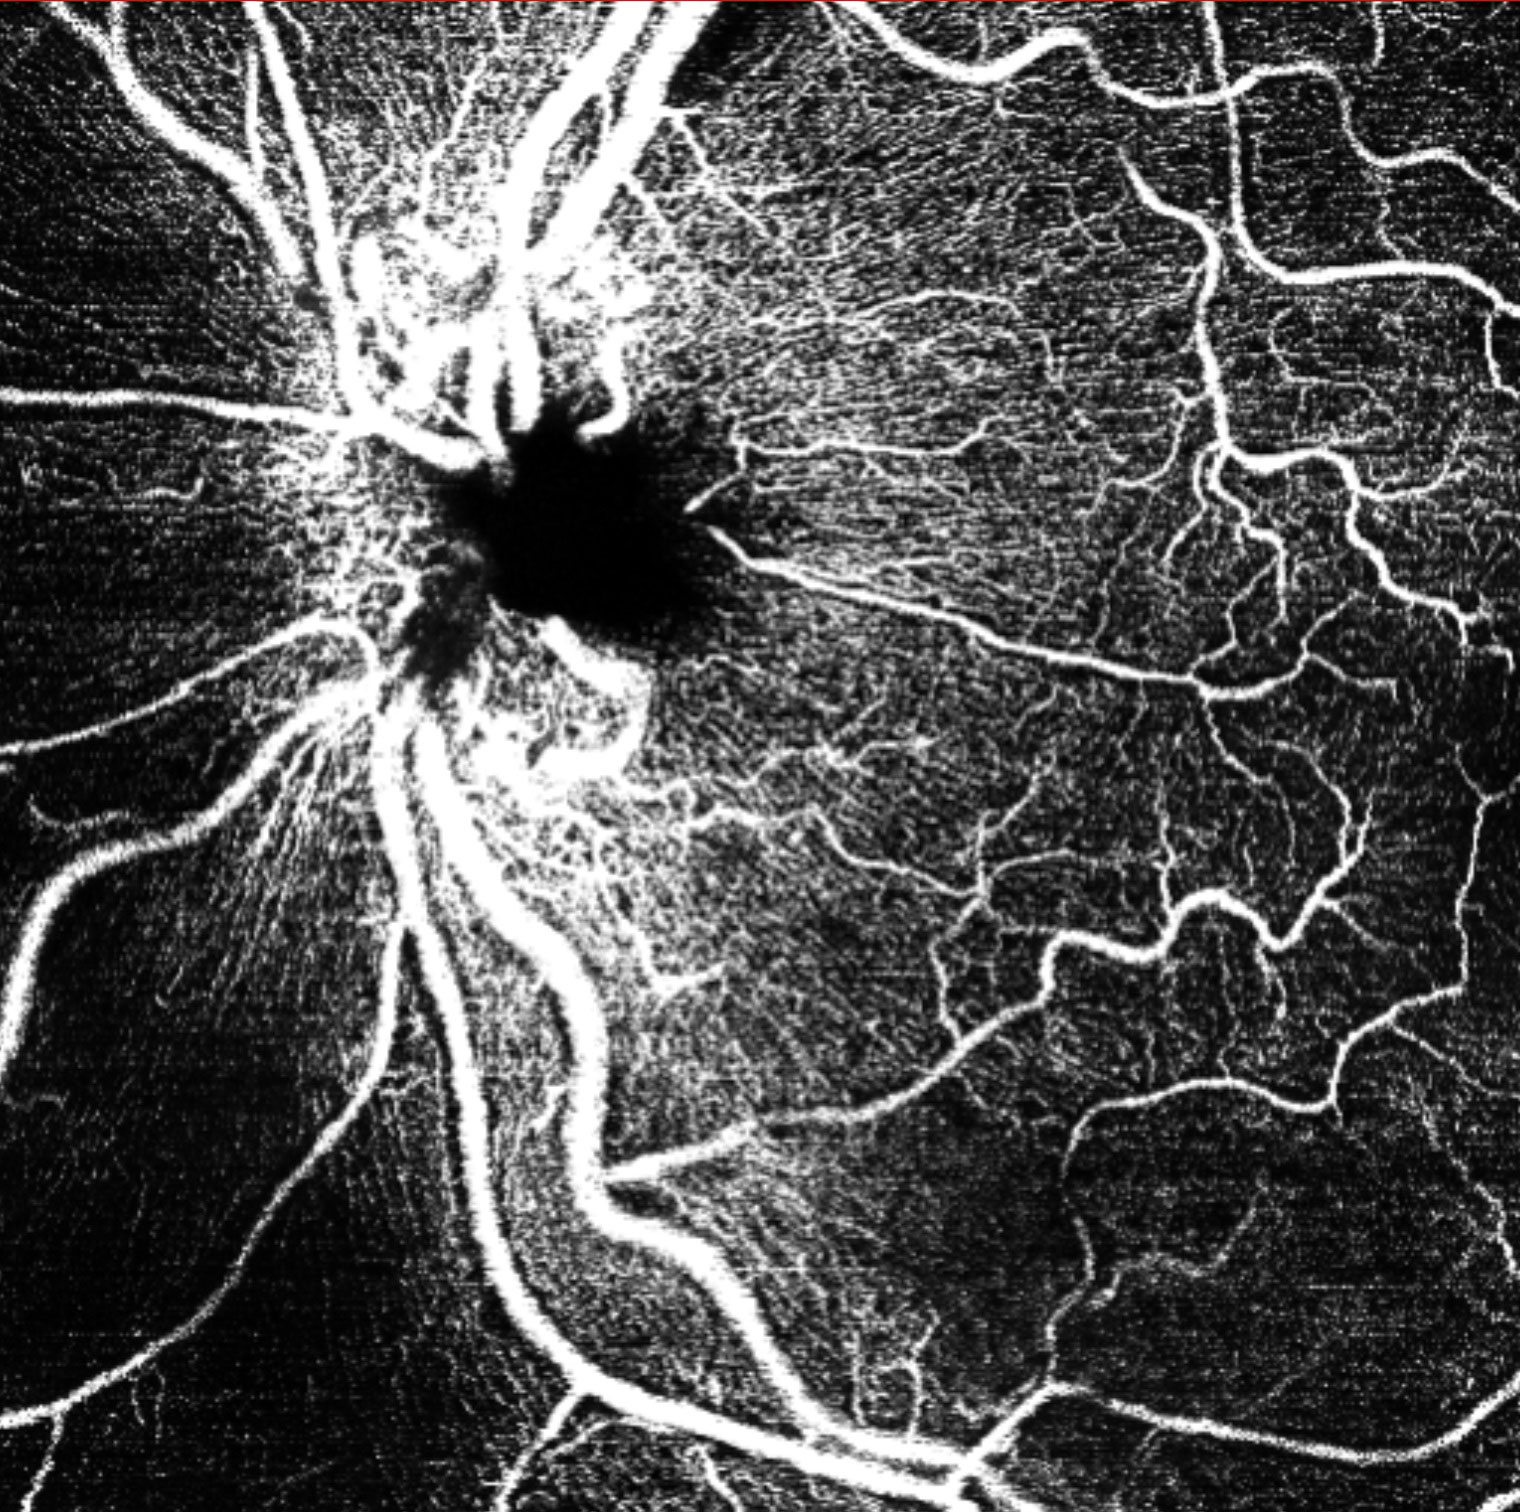

Offering the ideal speed-quality ratio for OCTA, 125 kHz allows you to increase your throughput without any clinically relevant loss in image quality in comparison to the current 85 kHz scan speed. The fast acquisition of images allows for visualization of flow, even in miniscule vessels, while minimizing artefacts, resulting in sharp and detailed images of the capillary network. Additionally, you can decrease chair time when you speed up acquisition with the Glaucoma Module Premium Edition in your glaucoma workflow, if applicable.

125 kHz – A fast scan speed for improved workflow and high OCTA image quality.